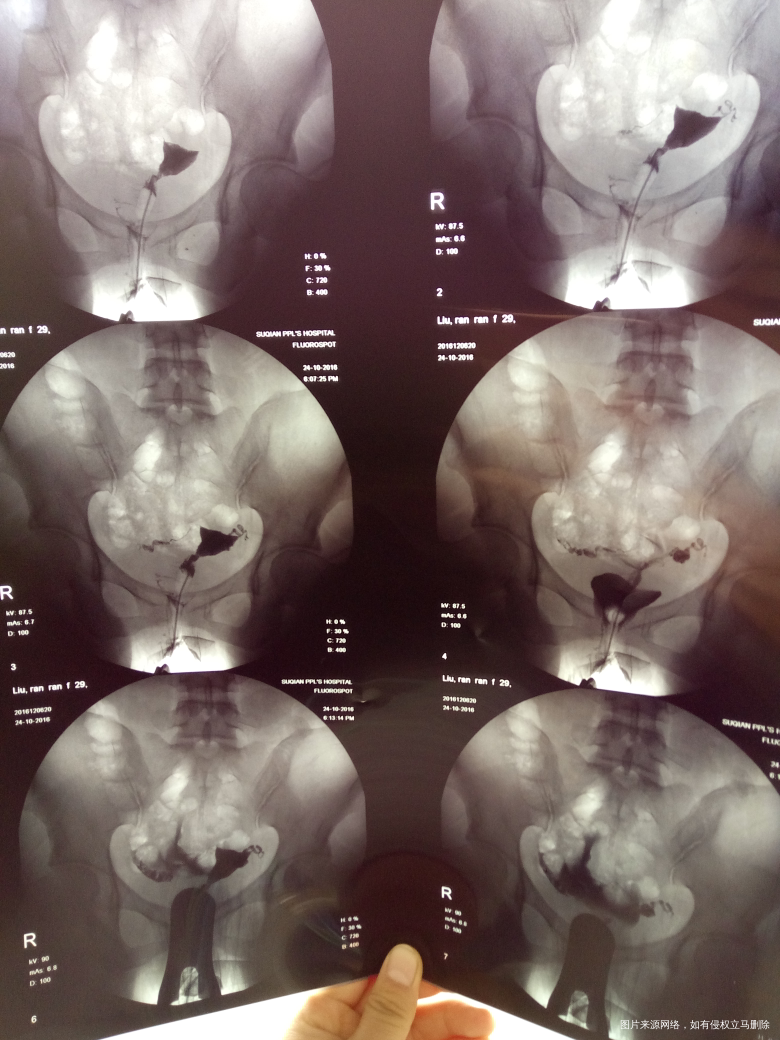

医生您好,结婚一年多未避孕结果还是没怀上,上月做造影检查说是一侧不太通畅另一个不通有积液。让这个月去做宫腔镜检查,结果本月去了后医生说这种情况要做宫腹腔手术治疗。没有其他办法。但是之前造影的时候是一侧管子可以进入,另一个输卵管两个医生一起放置都没把握放进去,说是试一下,结果刚开始推药管子就掉了,试了2次都是一推药管子就自动弹出来,造影剂就流出来。后面医生说我宫颈口小,输卵管前端呈弯曲状,现在的管子不好插进去,说如果之前老式管子可自动弯曲到时好用。我现在就不知道我这种情况到底算是怎么回事。到底该不该做宫腹腔手术,比较害怕